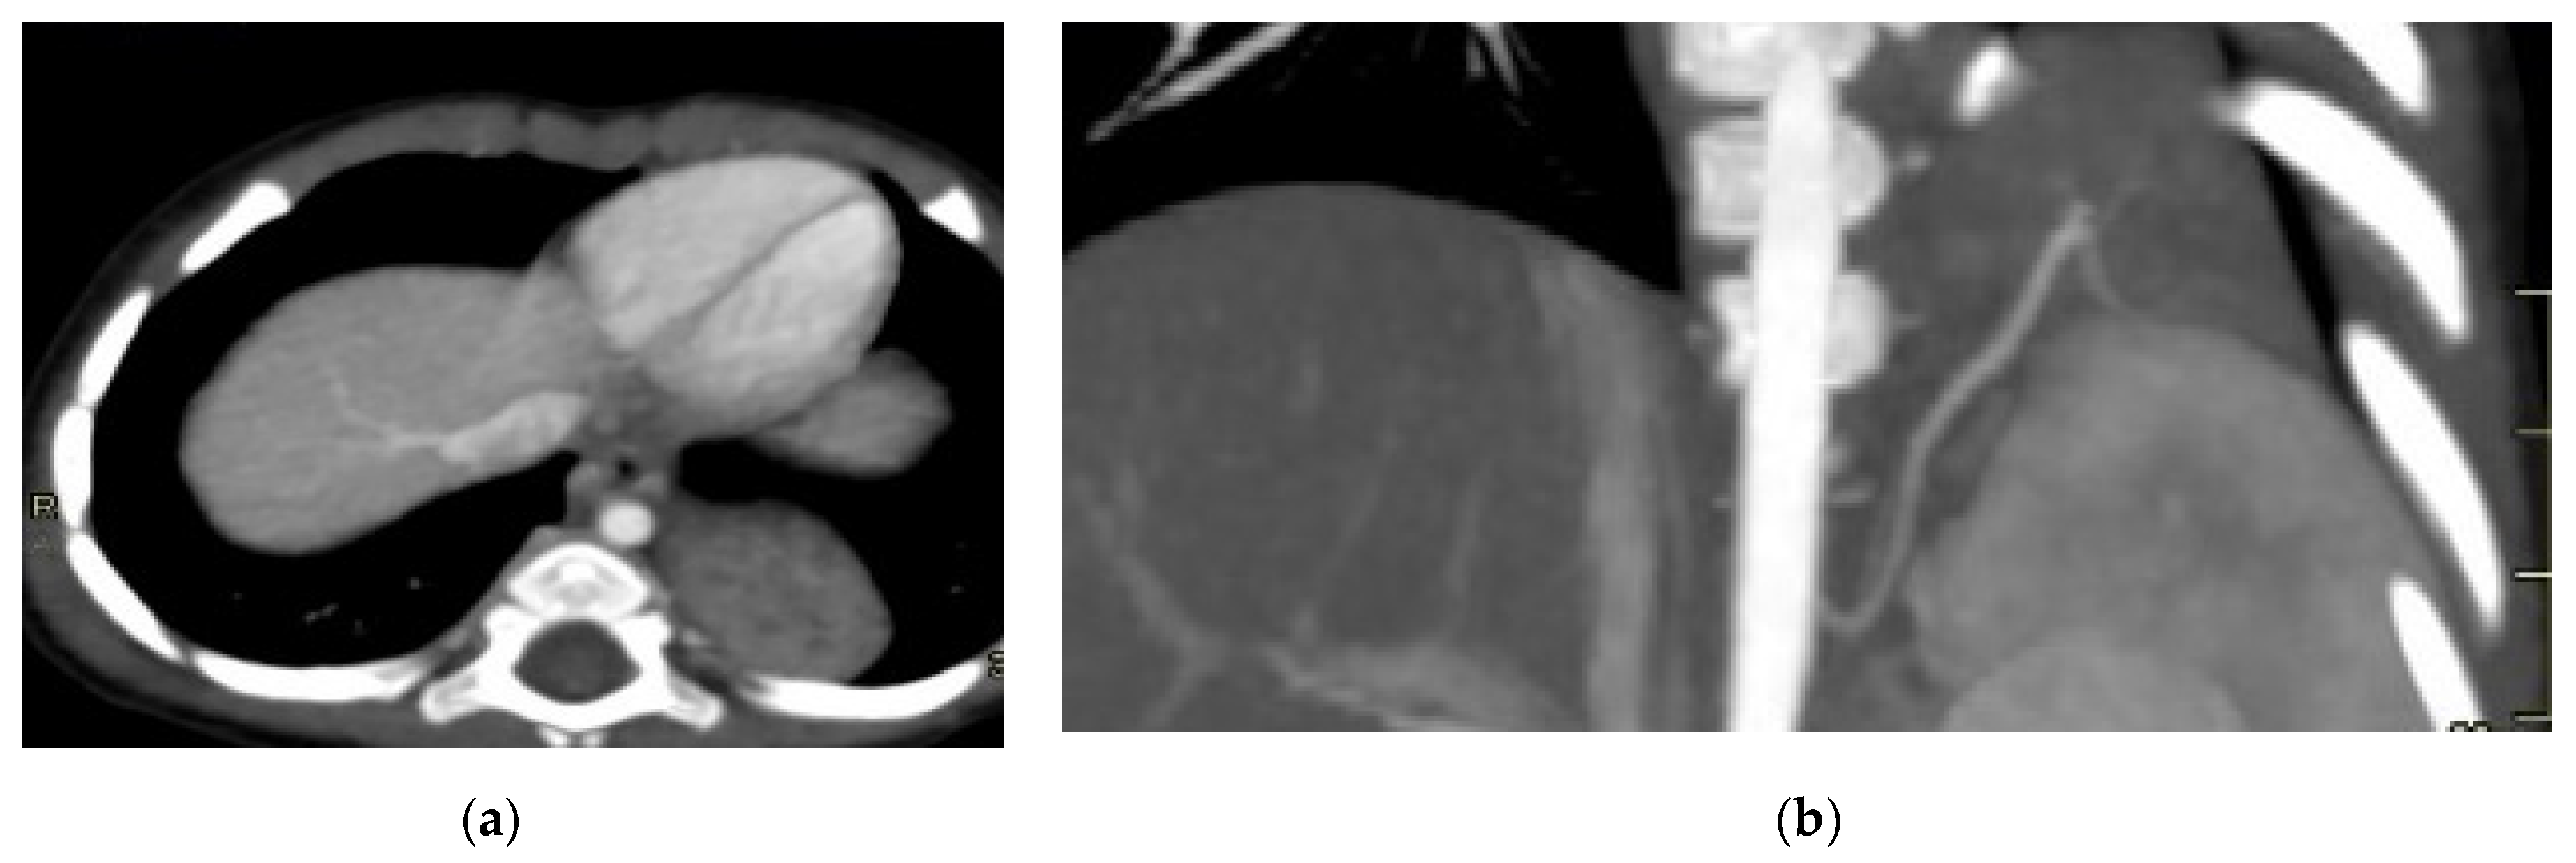

Figure 1. CPAM type I. HASTE oblique sagittal (a) and True FISP (b) MRI scans taken at 28 weeks of gestation reveal a large fluid-filled mass with bright T2 signal in the right chest (arrows). This abnormality results in a shift of the heart toward the left side of the mediastinum.